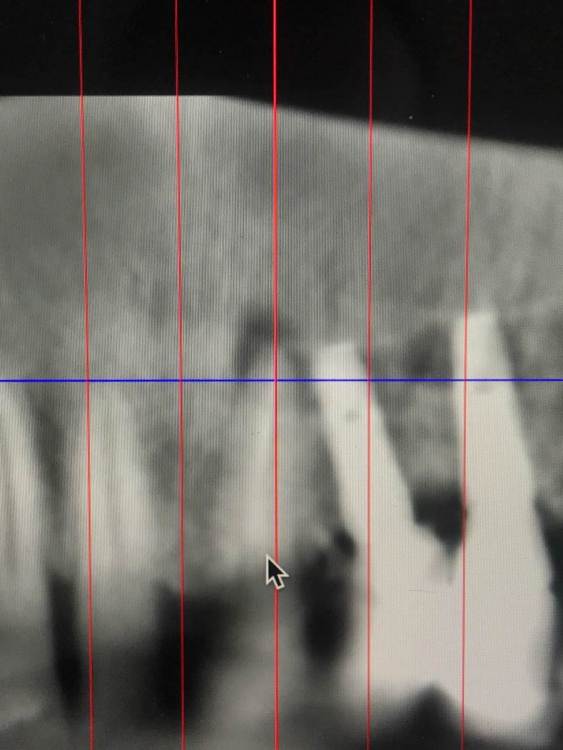

TIGER Опубликовано 1 октября, 2022 Поделиться Опубликовано 1 октября, 2022 Всем хорошего дня!Иногда некачественное эндо может привести к фатальным последствия,тут мы успели принять меры и сохранить и зуб и имплант!Вывод:эндо подготовка зубов прилегающих к зоне имплантации должна проводиться до имплантации!P.s винтик от НКР уже 7 лет там 3 Ссылка на комментарий

Женька Опубликовано 1 октября, 2022 Поделиться Опубликовано 1 октября, 2022 Классно получилось! По снимку до вроде эндо было? Ссылка на комментарий

TIGER Опубликовано 1 октября, 2022 Автор Поделиться Опубликовано 1 октября, 2022 @Женька Спасибо,да было,когда делали давно Ссылка на комментарий